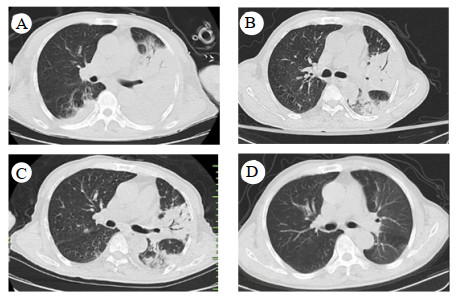

辅助检查:白细胞计数15.0×109/L,中性粒细胞百分比97.9%,淋巴细胞绝对值0.14×109/L,血小板计数344×109/L,血红蛋白94 g/L;降钙素原1.22 ng/mL,白介素6 87.5 pg/mL,C-反应蛋白254.5 mg/L;丙氨酸氨基转移酶171 U/L,天门冬氨酸氨基转移酶292 U/L,白蛋白24.7 g/L,肌酐186 μmol/L,尿素氮18.99 mmol/L,B型钠尿肽前体(pro brain natriuretic peptide, pro-BNP)3 301 pg/mL。胸部CT示两肺炎症渗出,左肺实变(图 1A)。经验性予美罗培南0.5 g每8 h一次联合莫西沙星400 mg每24 h一次抗感染治疗。行支气管镜检查留取肺泡灌洗液送痰培养和mNGS检测。在患者入院第2天,外周血mNGS检测到鹦鹉热衣原体,序列数166。改用美罗培南0.5 g每8 h一次(第1~10天)和多西环素片口服100 mg每12 h一次(第2~18天)抗感染治疗(图 2)。入院第3天的肺泡灌洗液mNGS回报鹦鹉热衣原体(序列数280)。痰培养、血培养、血隐球菌抗原、真菌G/GM试验均为阴性。入院第4天行腰椎穿刺检查,测得压力为240 mmH2O(1 cmH2O=0.098 kPa),脑脊液为无色透明,留取标本送常规、生化和mNGS。脑脊液结果提示有核细胞数为2×106/L,红细胞计数为22×106/L(参考范围 < 1×106/L),蛋白含量为34.8 mg/dL(参考范围8~43 mg/dL),葡萄糖含量为4.13 mmol/L(参考范围2.2~3.9 mmol/L)。入院第6天,脑脊液mNGS结果回报鹦鹉热衣原体(序列数4)。入院第8天复查腰椎穿刺的压力为185 mmH2O,留取标本送检。本次脑脊液常规和生化结果与第一次相仿,mNGS未检测到鹦鹉热衣原体。经过抗生素治疗(图 2),患者一般情况好转,炎症指标下降(图 3A、3B),脏器功能好转(图 3C、3D),复查胸部CT提示肺部病变吸收(图 1B),于入院第11天拔除气管插管改鼻塞吸氧,氧合99%,生命体征平稳。神志清,对答切题,语言流利,颈软。能稳准地完成指鼻试验和跟-膝-胫试验。于入院第18天出院。后随访患者恢复良好,无后遗症。住院期间头颅磁共振提示腔隙性缺血灶,未提示新发脑梗、脱髓鞘等病变(图 4)。患者出院后第5天和第44天查胸部CT见左肺渗出进一步吸收(图 1C、1D)。

| A为入院时,B为住院第16天,C为出院后5 d,D为出院后44 d 图 1 患者胸部CT影像 |